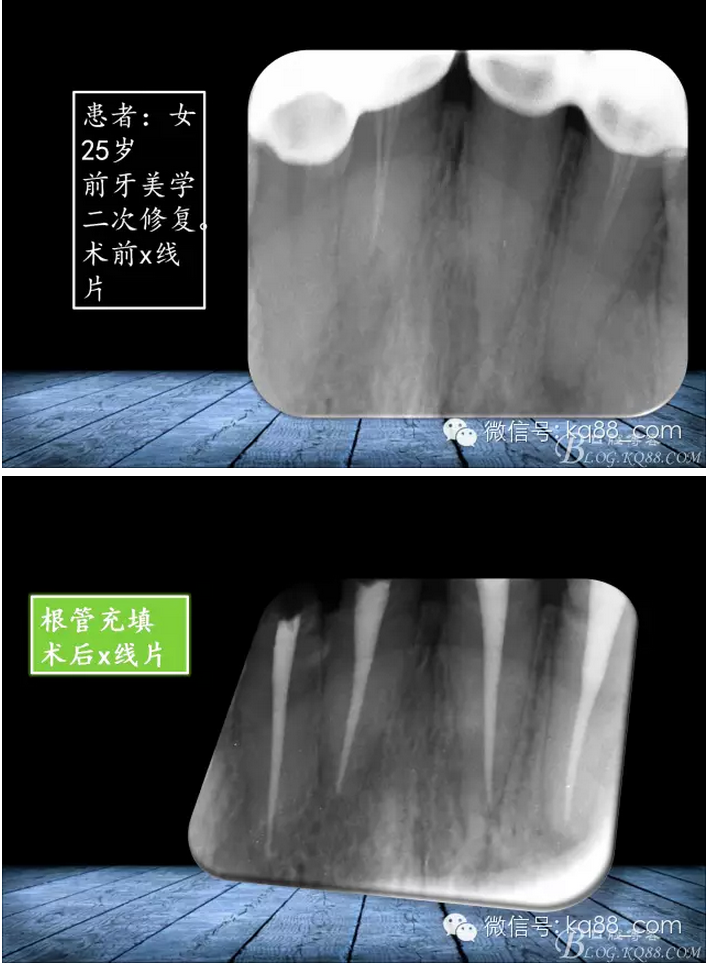

張瑞鋒:簡(jiǎn)單的事情認(rèn)真做——我的根管治療